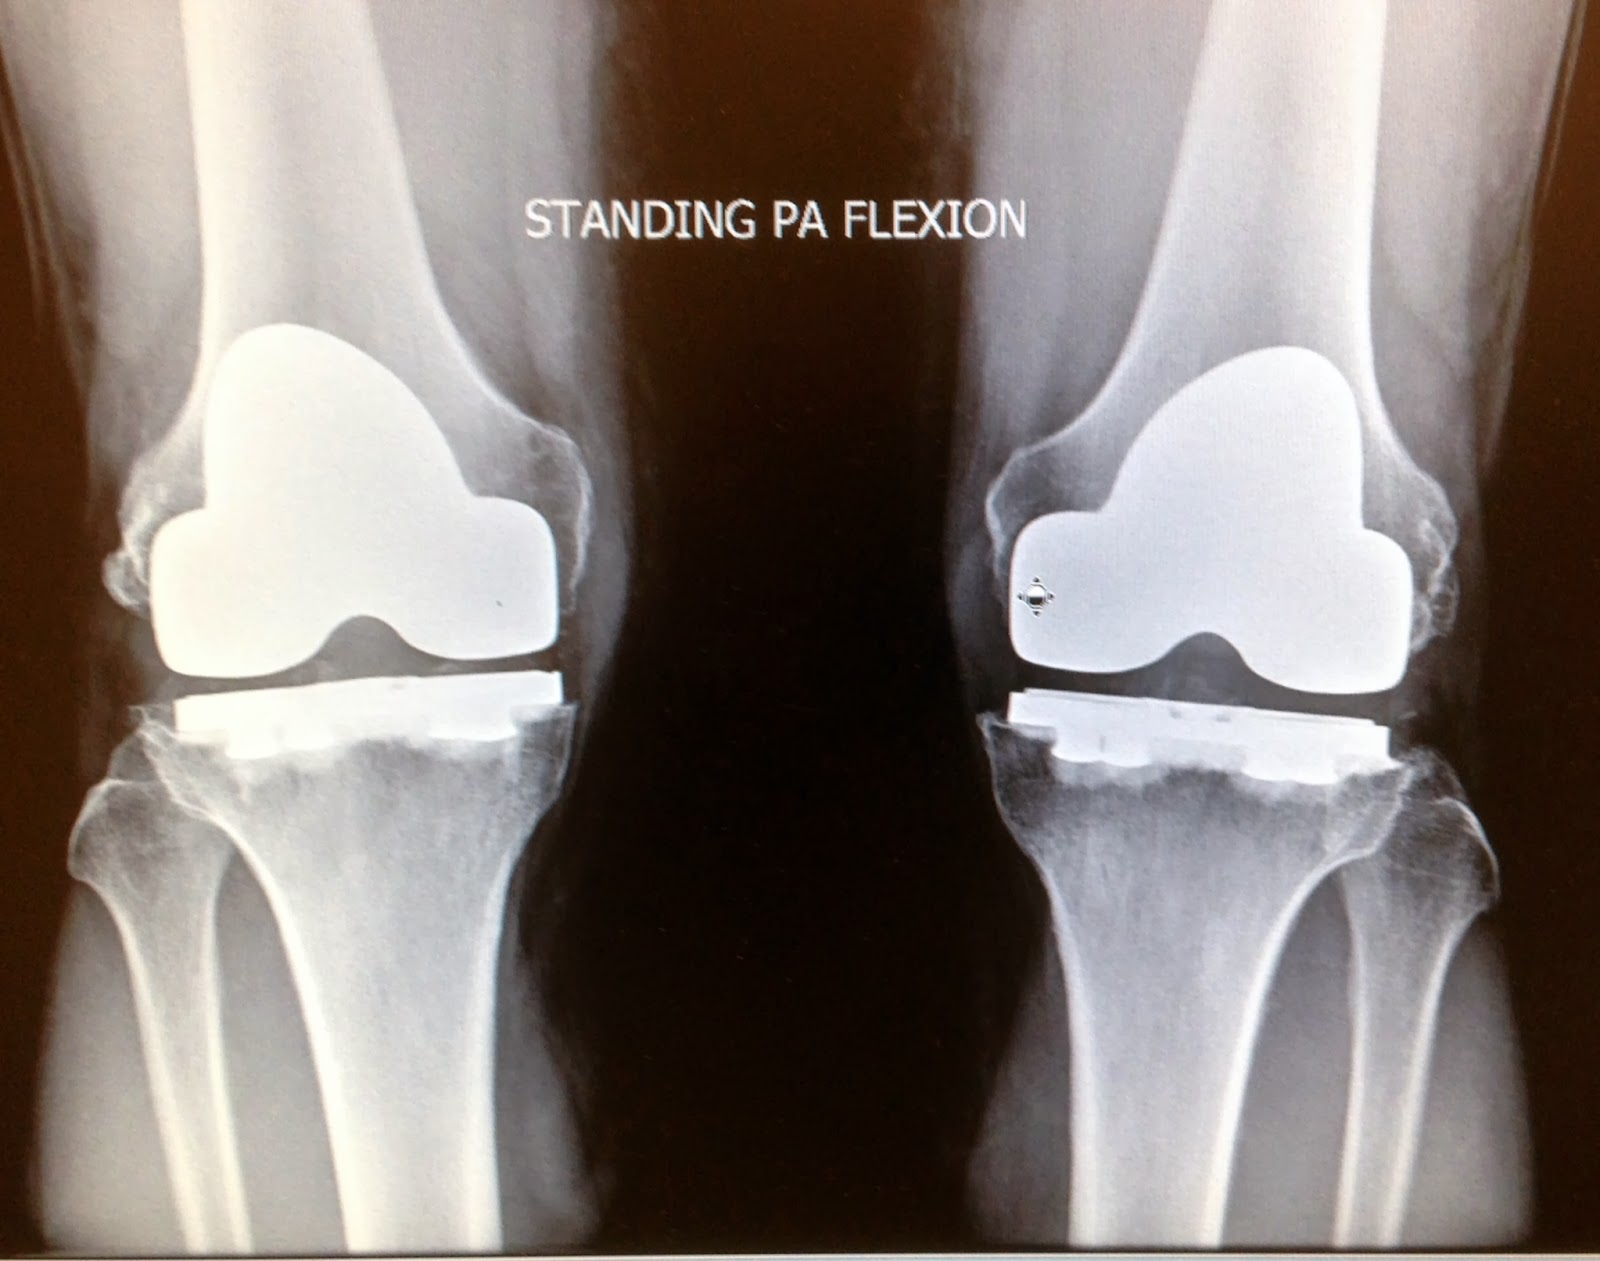

Xray image of an artificial knee joint Stock Photo Alamy Can You Kneel On A Artificial Knee    yes you can kneel after a total knee replacement! Doctors don’t know who can and who can’t kneel after. Kneeling can take 8 to 12 months before it is possible and comfortable. Some people find it uncomfortable or notice that it causes unusual sensations.   discover safe and effective exercises to improve kneeling abilities after total knee replacement surgery.. Can You Kneel On A Artificial Knee.

kneereplacementxray The Orthopedic & Sports Medicine Institute in Fort Worth Can You Kneel On A Artificial Knee  Some people find it uncomfortable or notice that it causes unusual sensations. It is possible to kneel on an artificial knee without damaging it. Kneeling can take 8 to 12 months before it is possible and comfortable.   after partial knee replacement, patients can kneel, but they need to be taught to do so: They also have concerns about living. Can You Kneel On A Artificial Knee.